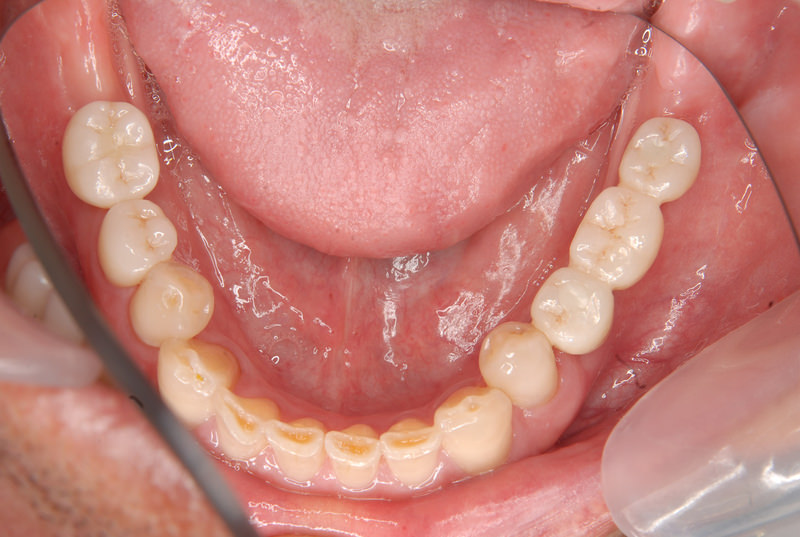

症例140代 男性 主訴 奥歯に歯を入れたい、しっかり噛みたい

治療前

治療後(5年経過)

主訴 奥歯がない為、食事が不自由である。入れ歯は煩わしいので、固定制のインプラントにして欲しいと訴え来院。口腔内全体で6本のインプラントを埋入。仮歯にて神経筋機構、顎関節のバランスを整え、リハビリを経て、約5ヶ月後にジルコニアを装着。

リスクとしては、外科的侵襲がある。デメリットは、保険外診療の為、経済的負担がある。

費用 316万(税込) (オペ・仮歯・最終補綴物まで含む)